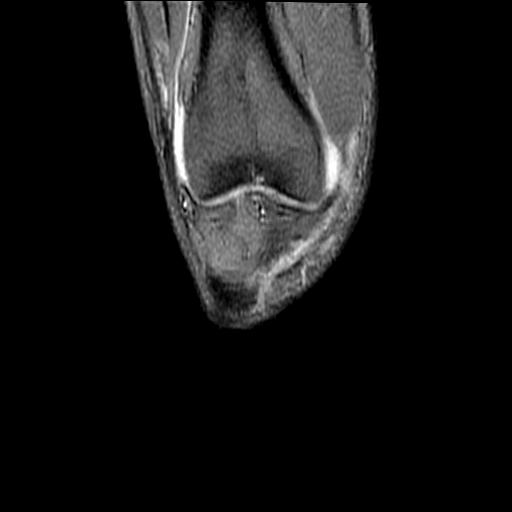

40岁男性,右膝关节外伤,x光平片示,髁间隆突撕脱骨折。

3、关节腔积液。

3、滑膜炎伴关节腔积液。

3、关节腔积液。4、髁间脊撕脱骨折。

除了关节积液外并无韧带撕裂,acl胫侧附着点有2束,正常情况下脂肪信号。此病例应加做压脂像以便观察是否有骨损伤。